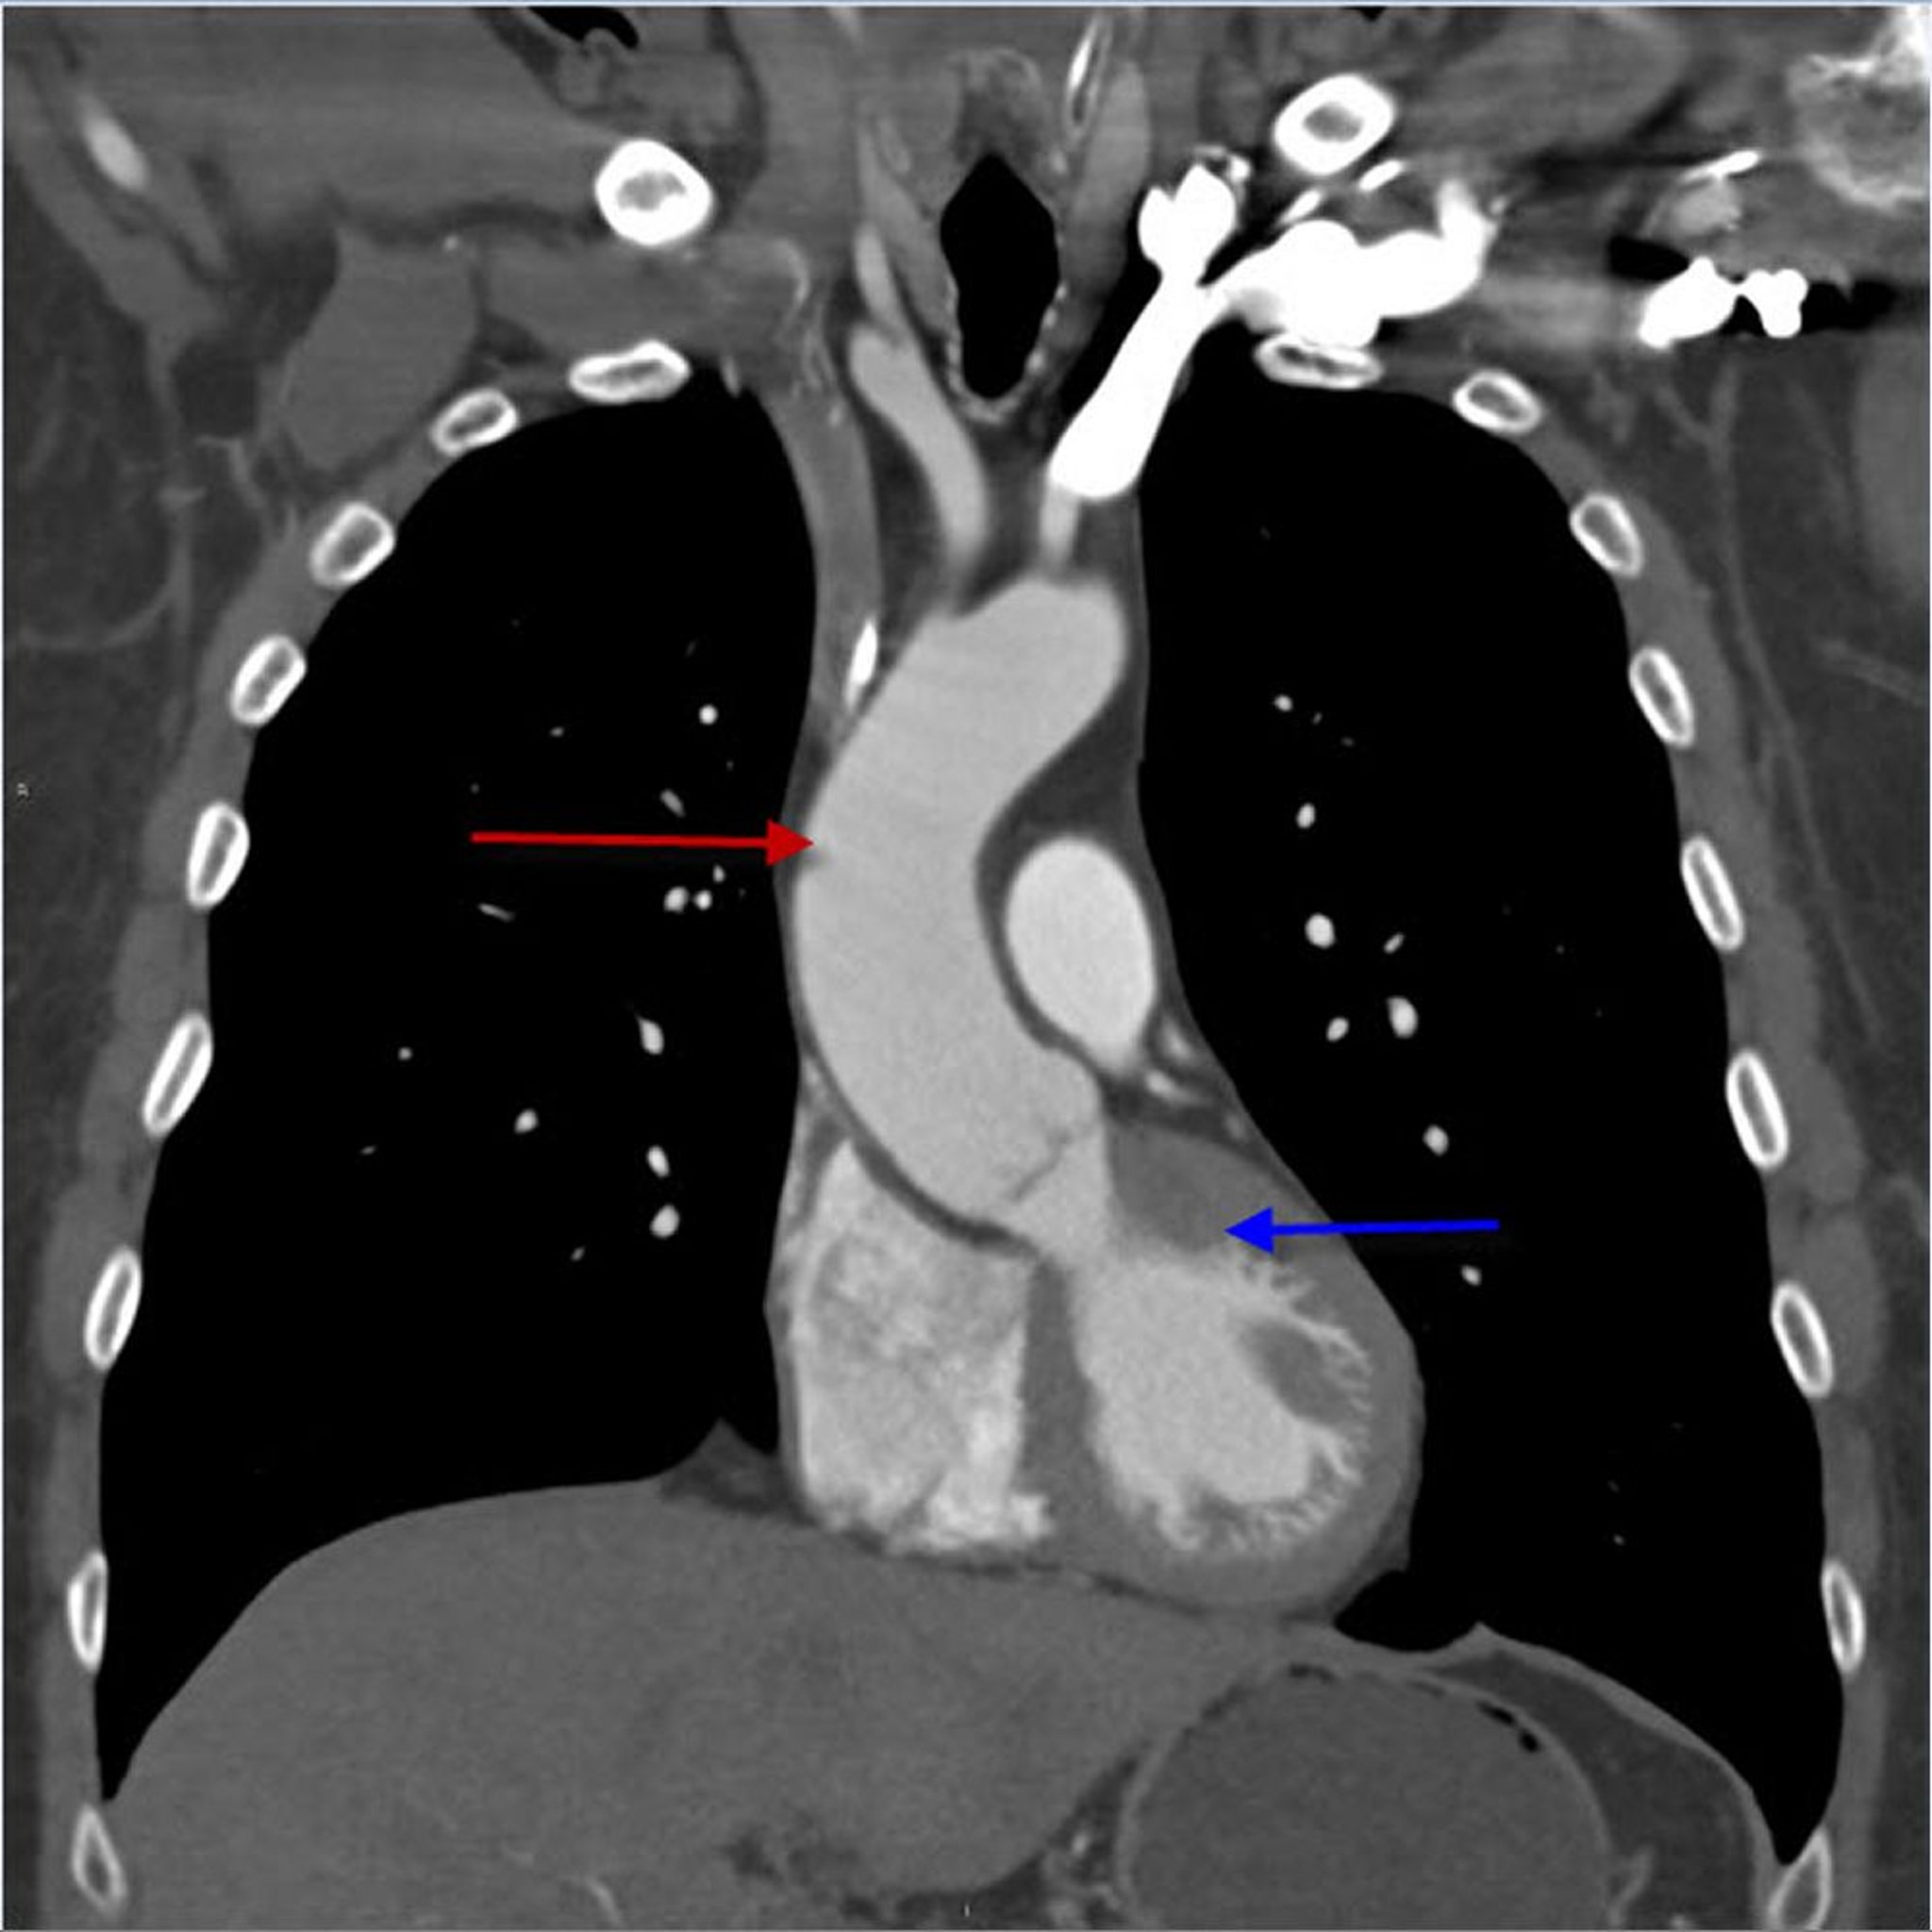

CTA (Coronal View) of Thorax Showing Ascending Thoracic Aorta

This image shows the ascending thoracic aorta (red arrow) arising from the left ventricle (blue arrow).